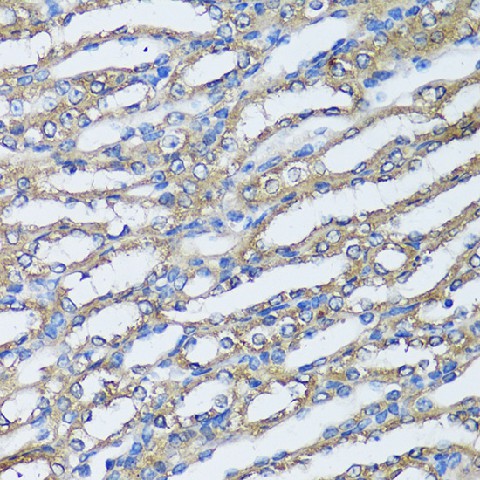

Immunohistochemistry of paraffin-embedded Human liver using NQO2 Polyclonal Antibody at dilution of 1:100 (40x lens).